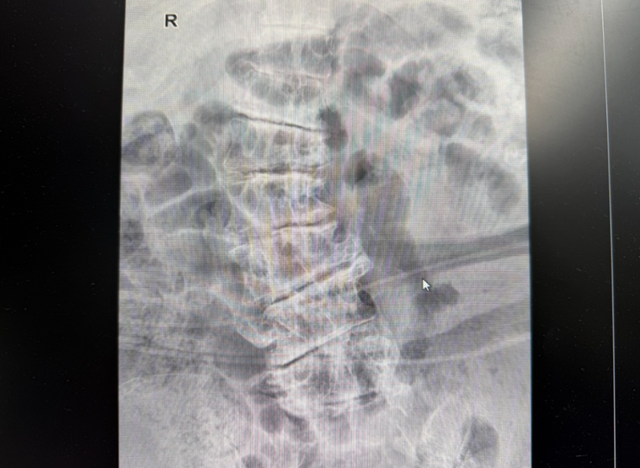

患者CT显示:

○ 脊柱侧弯

○ 胸12-骶1真空征

"患者脊柱侧弯畸形,传统手术需要剥离肌肉、植入钢钉,而PCD技术只需一根穿刺针就能解决问题!"尹绍猛指出。

○ 在C臂引导下将穿刺针精准送达病变椎间盘。

全麻后,在C臂引导下将穿刺针精准送达病变椎间盘。